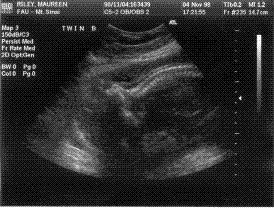

(Here is an image of Baby "B"

from Nov. 4, lying sideways, head on the left and body on the right,

facing down, with the spine clearly visible, connected to the skull on

the left) |